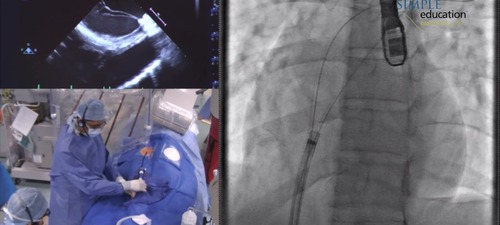

Sayan Sen provides commentary on this recorded live case of ASD closure performed by Dr Iqbal Malik.

Procedural steps covered include: